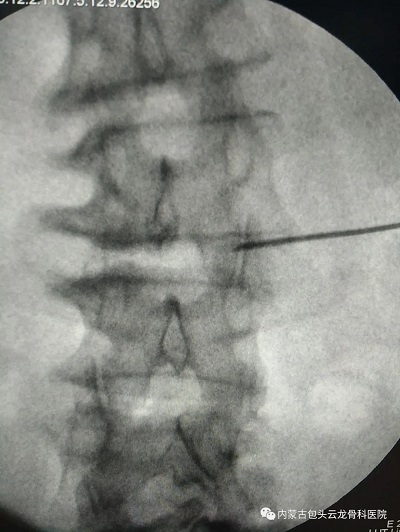

小杰和家人经过深思熟虑,决定接受这种治疗方式。治疗当天,小杰躺在了治疗床上,在C臂透视下,将针头精确地刺入病变神经根的周围,然后注入混合药物。整个过程并不痛苦,小杰感到腰部有些轻微的胀痛,但可以接受。

椎间孔硬膜外神经阻滞术手术影像